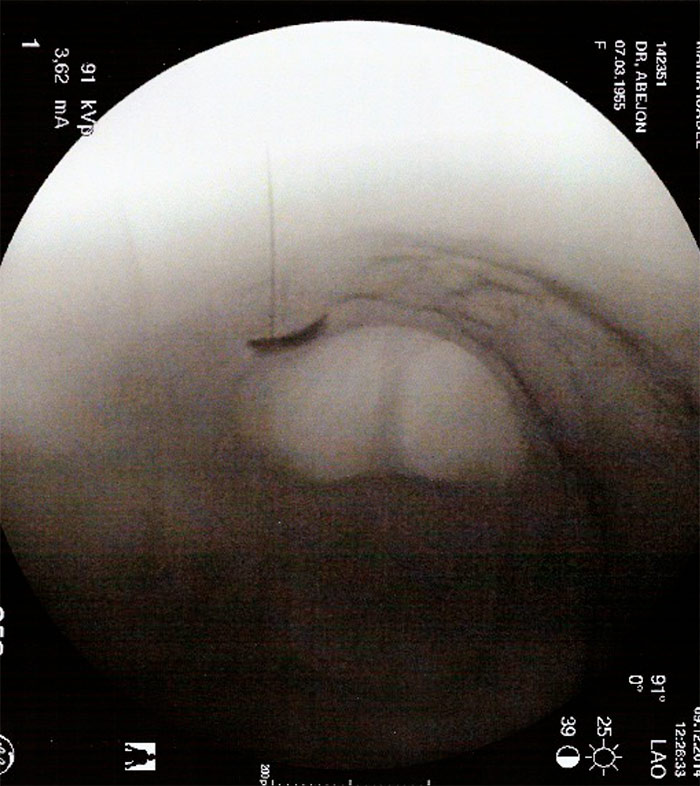

Existen diversos abordajes para realizar el bloqueo o la radiofrecuenica de esta estructira. Se describe un abordaje lateral Con el arco de fluoroscopia en posición lateral para buscar el target,  que en este abordaje es el espacio interdiscal coxigeo. En esta posición y siempre viendo el disco intercoxígeo se realiza la punción hasta atravesar atravesar el espacio interdiscal donde notaremos una pérdida de resistencia del ligamento sacrocoxigeo anterior. Se comprueba con contrste radiopáco la posición óptima de la aguja, la distribución del mismo será en la cara anterior del sacro.